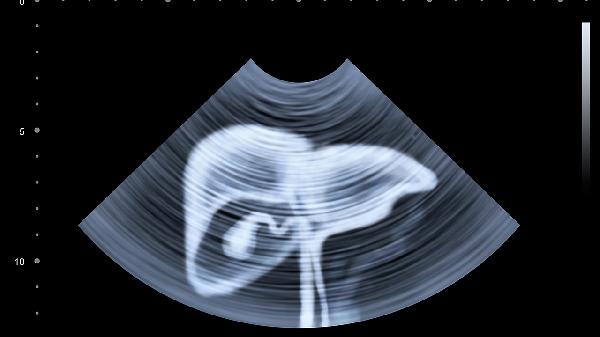

超声、CT等影像学检查才是诊断的关键。甲胎蛋白只是线索之一,就像破案需要多方证据。

2、完善肝脏检查

肝功能、乙肝五项、肝脏超声都是必查项目。全面评估比盯着一个数字更有意义。